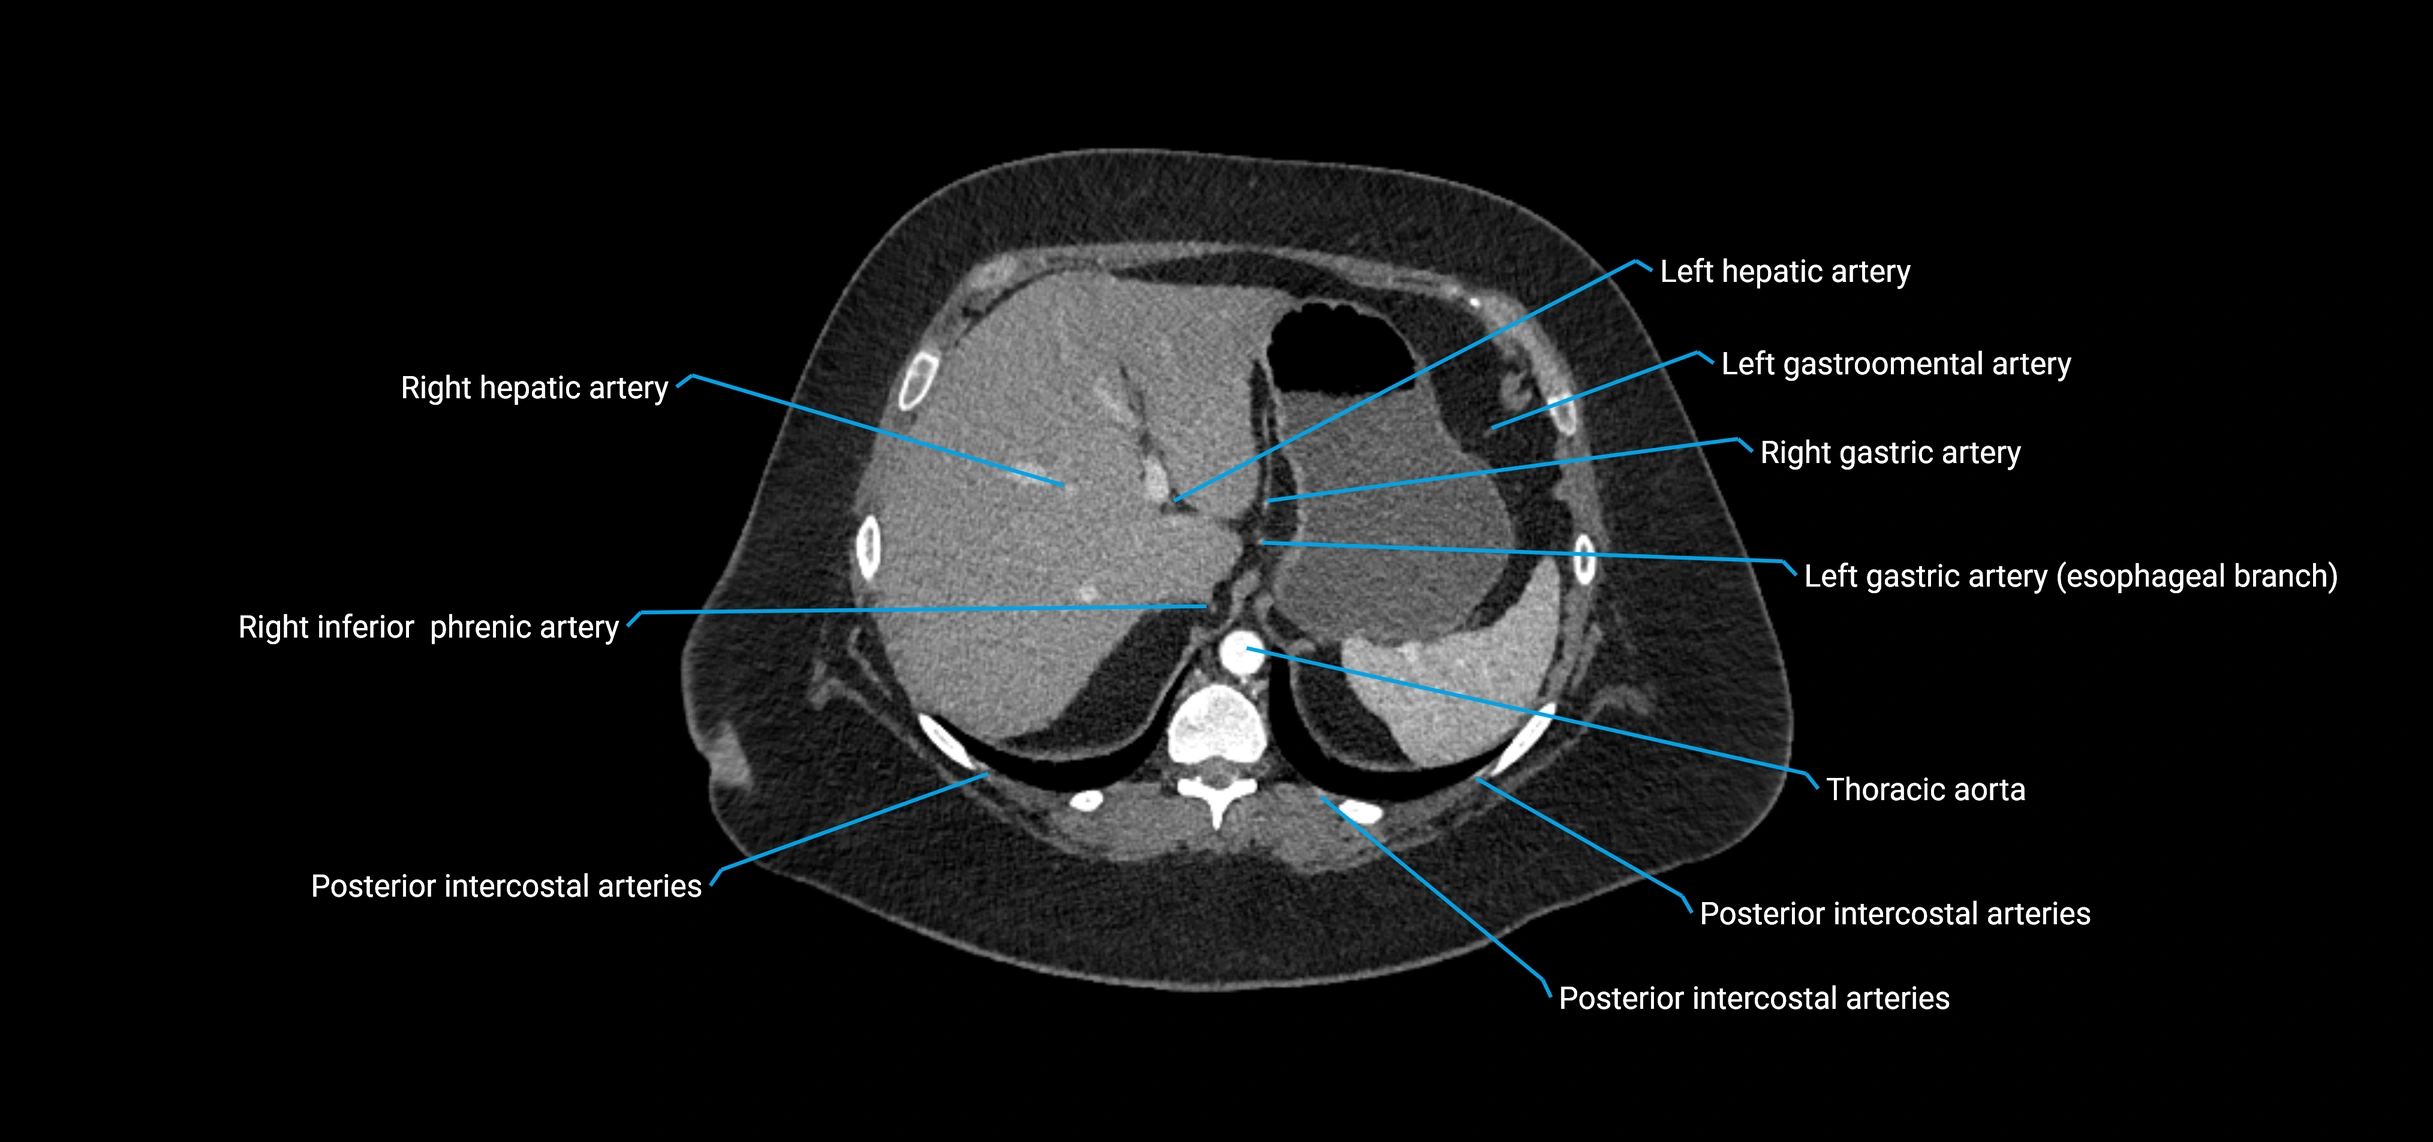

CT images

image

Contrast-enhanced CT (CTA):

• Gold standard for abdominal aortic imaging

• Provides excellent detail of lumen, wall, aneurysm, thrombus, and branch vessels

• Multiplanar and 3D reconstructions help in aneurysm measurement, stent graft planning, and dissection evaluation